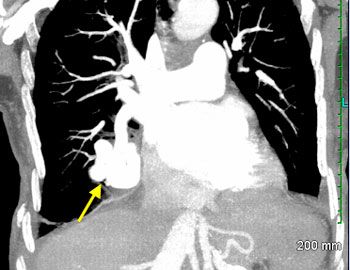

A CT scan of the chest with contrast revealed a right infrahilar large (4 cm) pulmonary arteriovenous malformation (PAVM) (Figure). A contrast echocardiogram (TTE with bubble study) revealed significant delay before bubbles appeared in the left atrium-a finding that confirmed the intrapulmonary shunt. The patient was transferred to another facility for embolization therapy.

The majority of PAVMs are found in the lower lobes. They can manifest as single or multiple lesions and as unilateral or bilateral disease. PAVMs can also be categorized as simple (all feeding arteries arising from a single subsegmental artery with drainage through a single vein) or complex (perfused by more than one subsegmental artery with 2 or more draining veins). On chest films, PAVMs appear as oval, round, or occasionally bilobular pulmonary nodules. Diameter can range between a few millimeters to several centimeters.

Shunt fraction is elevated in nearly all patients with clinically significant PAVM.1 A shunt fraction <5% determined by the 100% oxygen method is deemed abnormal and warrants additional workup.1 Direct imaging studies provide the evidence required for a definitive diagnosis. Chest radiography will reveal some abnormality and chest CT with contrast discloses greater detail of the vascular anatomy than a plain chest film.